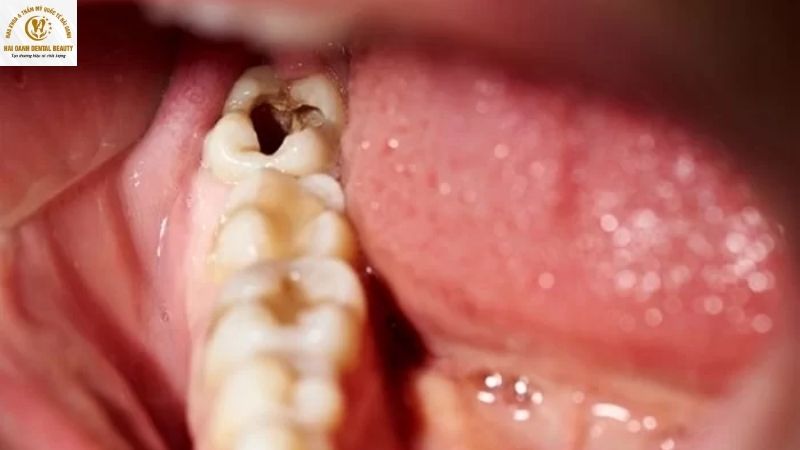

Răng khôn, hay còn gọi là răng số 8, là chiếc răng mọc cuối cùng trên cung hàm, thường xuất hiện ở độ tuổi từ 18 đến 25. Vị trí đặc biệt của nó không chỉ gây ra các vấn đề về mọc lệch mà còn khiến nó trở thành mục tiêu dễ bị tấn công bởi vi khuẩn gây sâu răng.

1.1. Vị trí mọc quá sâu và khó vệ sinh

Đây là nguyên nhân phổ biến và quan trọng nhất. Do nằm ở vị trí tận cùng trong hàm, việc tiếp cận để chải rửa răng khôn là cực kỳ khó khăn, ngay cả khi nó mọc thẳng. Bàn chải và chỉ nha khoa không thể làm sạch triệt để các kẽ răng và bề mặt răng, khiến mảng bám và thức ăn thừa dễ dàng tích tụ. Sự tích tụ này là môi trường lý tưởng cho vi khuẩn sinh sôi, tấn công men răng, gây ra tình trạng sâu răng.

1.2. Răng khôn mọc lệch hoặc mọc ngầm

Khi răng khôn mọc lệch, mọc ngang hoặc mọc ngầm, nó sẽ tạo ra một khoảng trống nhỏ giữa nó và răng số 7 bên cạnh. Khoảng trống này hoạt động như một cái bẫy, giữ lại thức ăn và vi khuẩn. Vì không thể vệ sinh sạch, vi khuẩn sẽ phát triển mạnh mẽ, gây sâu răng, không chỉ ở răng khôn mà còn có thể lan sang cả răng số 7, dẫn đến những hậu quả nghiêm trọng hơn.